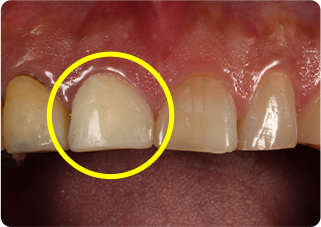

矯正的挺出・歯冠長延長術・セラミッククラウン症例①

術前

MTM、歯冠長延長後

術後

| 主訴 | むし歯の歯を抜きたくない |

|---|---|

| 治療期間/回数 | 5ヵ月、10回 |

| 価格(税込) | 154,000円(税込) |

| リスク・副作用 | セラミックの破損・脱離が生じる場合がある |

| ポイント | 通常だと抜歯と診断されるが、局所矯正と外科処置を行い、歯根を持ち上げることで、被せ物が可能になった。歯根を持ち上げたことにより長期的に安定した被せ物が可能になる。 |